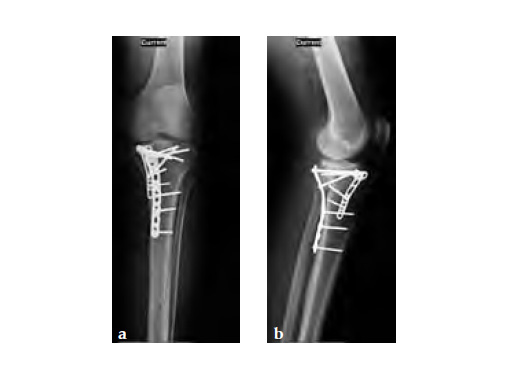

The system consists of six anatomically precontoured plates (1, 2, 4, 6, 8, or 10 shaft holes) with a range of six lengths (72-186 mm). The low profile plate head limits soft-tissue irritation and features four locking holes; one slotted for ease of plate positioning. The 3.5 mm LCP holes in the shaft enable fixation of posteromedial fragments with locking or non-locking screws.

A 33-year-old male was involved in an altercation and suffered a gun shoot wound to his knee

Initially taken for incision and drainage and then ORIF . Patient placed in a floppy lateral position with the effected lower extremity externally rotated (opposite hip and shoulder bumped up about 3040) allowing exposure of the posterior medial knee. A posterior medial and an anteromedial incision were used to repair the fracture with a 67 cm skin bridge.

Postoperative healing was uneventful and the patient had no complications.